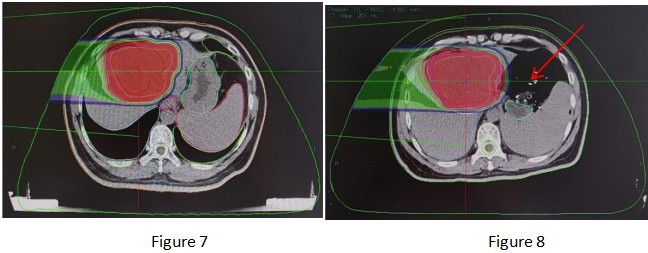

Based on the above imaging examinations, the patient currently has no evidence of distant metastasis, and carbon ion therapy can be performed. On March 4, 2025, the patient underwent radical carbon ion therapy for malignant hepatic tumors. The patient was treated in the prone position. The GTV was delineated based on the hepatic lesions visible on the positioning CT, abdominal MRI, and PET-CT; the ITV was delineated based on the hepatic lesions in all respiratory phases combined with 4D-CT; the GTVm was delineated based on the portal vein tumor thrombus visible on the positioning CT, abdominal MRI, and PET-CT; the CTV was GTV + GTVm + 5 mm, and the CTV was expanded by 5 mm to form the PTV; the PTVboost1 was the PTV avoiding the stomach, small intestine, and duodenum by 8 mm (as shown in Figures 1 and 2).

Prescription dose: PTV: 40 Gy (RBE)/9 fractions; PTVboost1: 8 Gy (RBE)/2 fractions (as shown in Figure 3).

After the verification was passed and the errors were eliminated, the patient received a single high-dose radical radiotherapy. The intraoperative radiotherapy dose was 20 Gy (RBE)/1Fx.